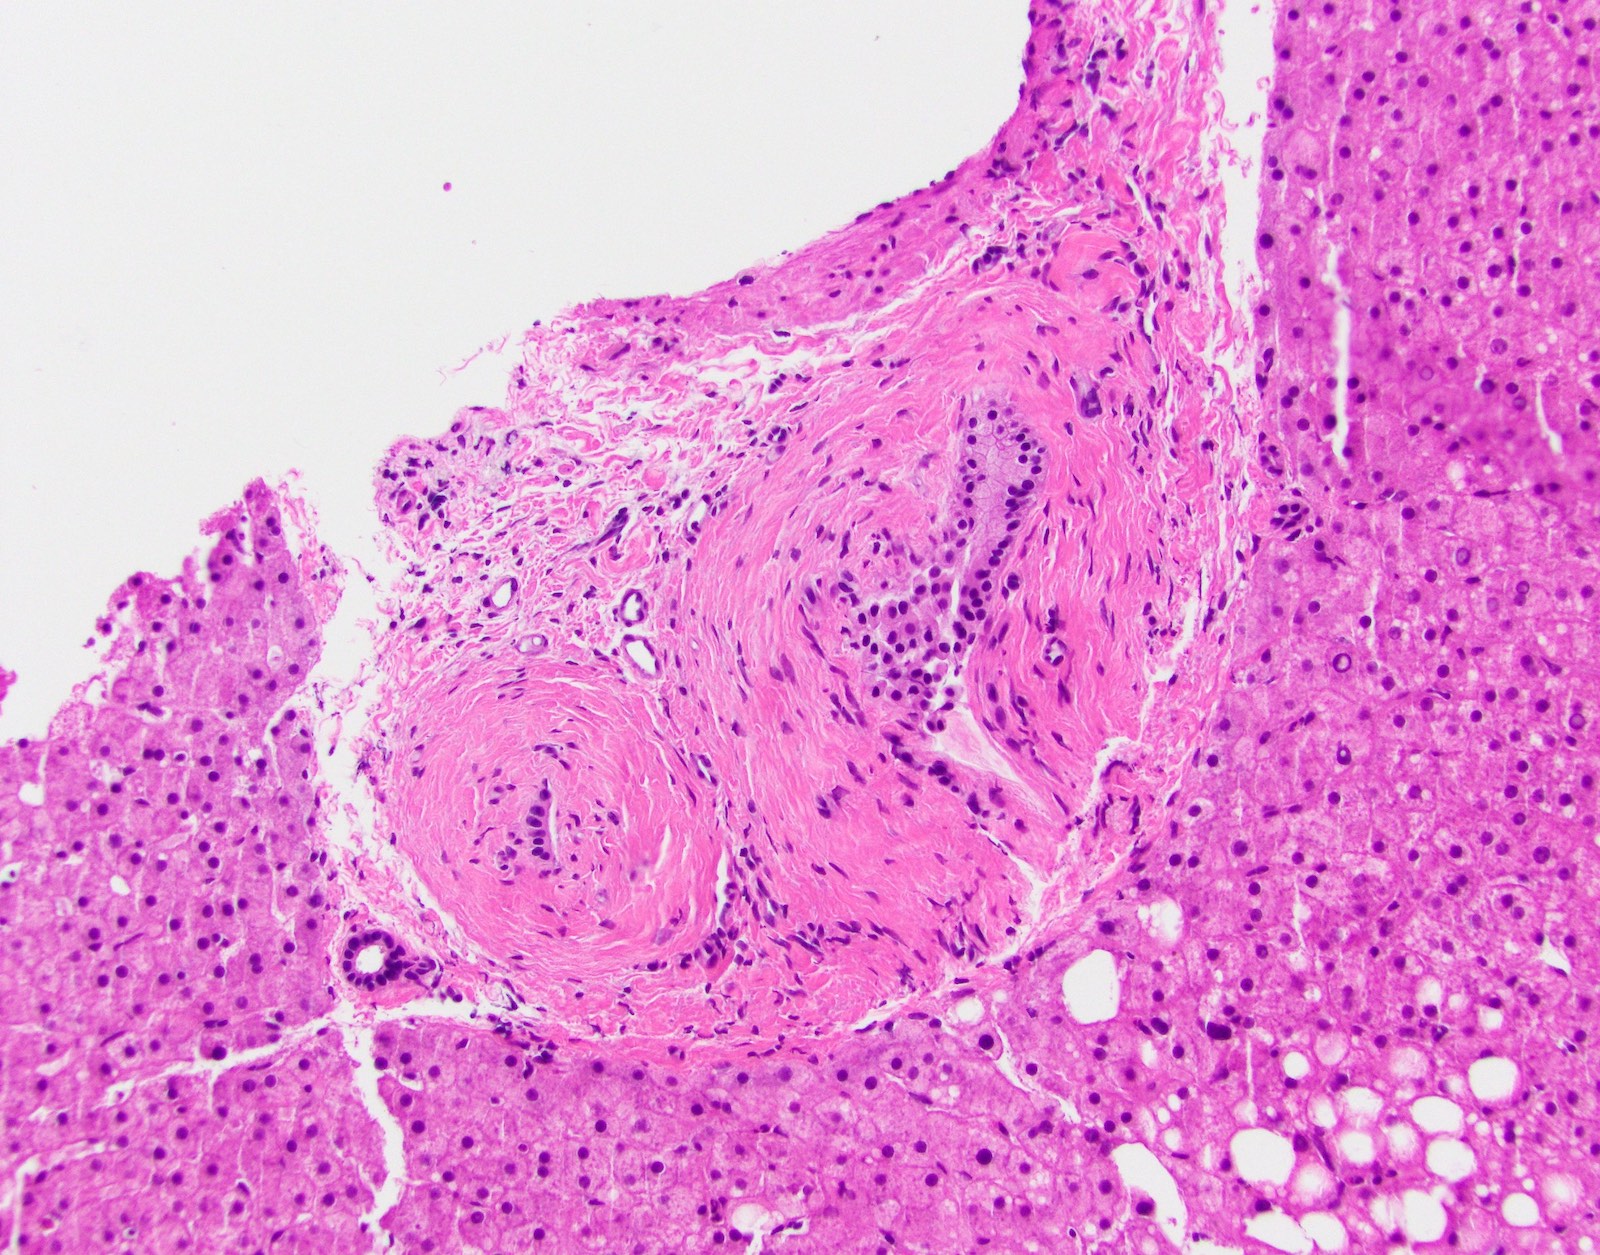

- Vascular changes (Pediatr Transplant 2018; 22:e13124, Am J Transplant 2018;18:1534):

- Obliterative portal venopathy with nodular regenerative hyperplasia-like changes

- Obliterative arteriopathy or isolated arterial "V" lesions (age inappropriate arterial fibrointimal hyperplasia with no T cell mediated rejection) with or without intimal inflammation arterial lesions are associated with subsequent T cell mediated rejection (TCMR), graft failure and C4d positivity; most C4d positive cases show additional histologic features encountered in cAMR such as portal and perivenular inflammation (rejection activity index / RAI 1 - 2) and at least moderate periportal, perivenular or sinusoidal fibrosis (Am J Transplant 2018;18:1534)

Microscopic (histologic) images